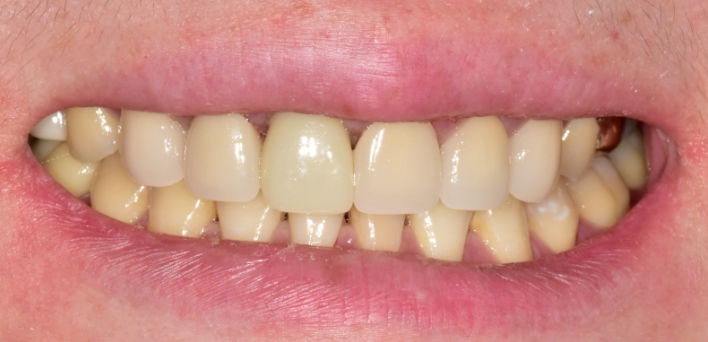

임플란트 : 손 ** 님 (50대)

치아가 있다는게, 아직도 정말 꿈만 같아요.

Before Before

After After

※ 더서울치과의원은 의료법을 준수하며 위 케이스는 실제 환자의 동의를 얻은 사례로 치료 전, 후가 동일한 환경에서 촬영되었습니다.

환자 케이스에 따라 부작용이 발생할 수 있습니다. 이 부분은 의료진의 충분한 상담과 체크를 통해 예방하고 줄일 수 있습니다.

[임플란트 부작용] 수술 후 관리가 소홀할 경우 출혈, 주위염 등의 부작용이 발생할 수 있어 구강 위생을 철저히 유지하고, 정기적인 검진을 통해 상태를 점검하는 것이 중요합니다.

환자 특징

환자 특징01무치악 상태

환자 특징02수년간 무치악으로 지내심

임플란트가 불가능할것이라

생각하고 내원

위, 아래 6개씩 식립

디지털 풀아치 임플란트